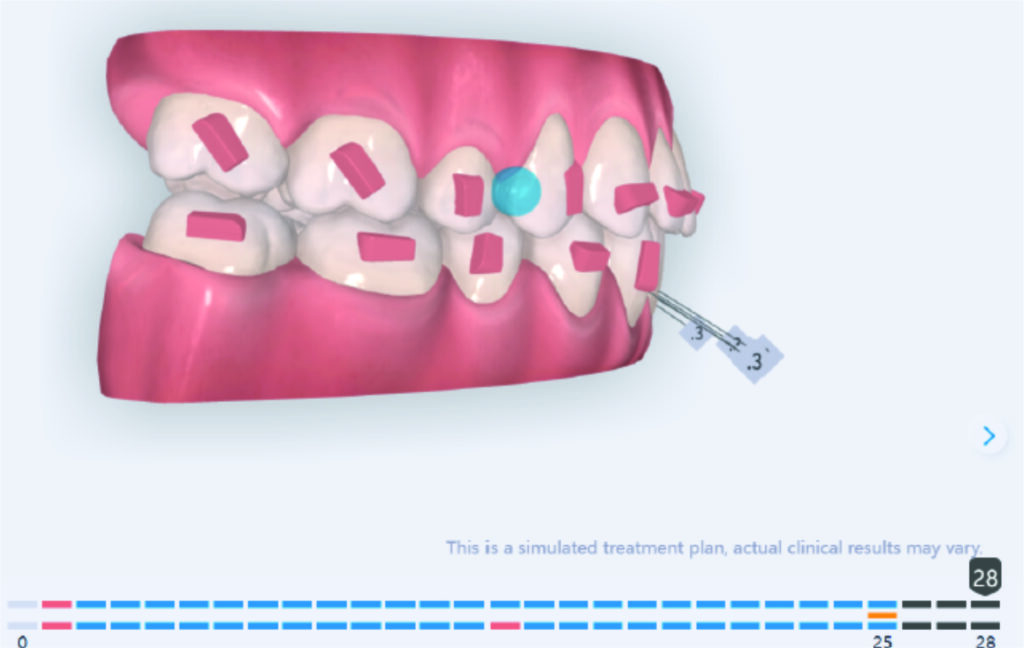

Derotation 26. IZC anchorage.

A 1.5 mm deviation of the upper dental midline to the patient’s left was noted, along with a slight mandibular midline shift to the right, likely due to asymmetrical mandibular growth observed in the facial structure. Severe mesial rotations of teeth 16 and 26 were evident in the initial records. As derotation of 16, 26, 17, and 27 progressed up to aligner 16, the premolars in segments I and II moved distally, resulting in a bilateral Class I relationship, as intended in the initial treatment plan.

Derotation of 16 26 allowed Class II correction.

Vertical vector of elastic traction on buttons and IZC helped with the open bite correction.

No sequential distalization for Class II tendency correction was performed due to skeletal anchorage. Lingual attachments were used to improve aligner grip and control tooth movement, as small, angulated lower incisors are difficult to move due to limited anatomy.

An infrazygomatic crest (IZC) screw with force applied between the upper premolars produces a clockwise rotation of the maxillary occlusal plane. This movement aids in closing the anterior open bite and improves upper incisor display. IZC screws with elastics also enable planned intrusion of the upper molars by 1 mm. Because mandibular derotation after upper posterior correction is difficult to predict, anterior distalization and midline correction were performed in the later stages of treatment.